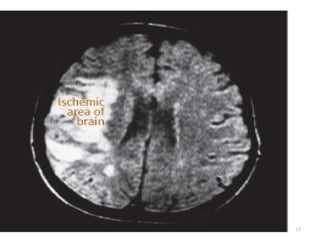

Cerebrovascular Accident

Ischemic – Thrombotic Stroke

 Lumen of the blood vessels narrow – then

becomes occluded – infarction

Associated with HTN and Diabetes Mellitus

>60% of strokes

50% are preceded by TIA

Lacunar Stroke: development of cavity in place of

infarcted brain tissue – results in considerable

deficits – motor hemiplegia, contralateral loss of

sensation or motor ability

13